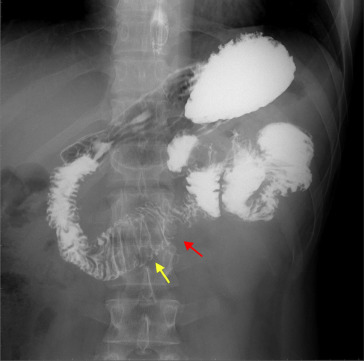

A 28-year-old man without any underlying disease presented with dizziness and general malaise for 6 months. He came to the clinic for help initially. Vital signs and physical examination were normal. Blood tests revealed only the following abnormality: hemoglobin 8.6 g/dL. His fecal occult blood test result was positive. Esophagogastroduodenoscopy and colonoscopy showed nonspecific findings. Ferrous sulfate was prescribed for suspected iron-deficiency anemia. Owing to refractory anemia, he was transferred to our hospital for further evaluation. Small bowel series showed a jejunal polypoid lesion with increasing folds and lumen dilatation in the jejunum (Fig. 1 ). Computed tomography of abdomen and pelvis showed soft tissue mass (4.8 cm × 2.5 cm) within a proximal jejunal loop and intussusception of jejunal loops (Fig. 2 , yellow arrow). This patient received surgical resection. A long-stalk mass (about 4 cm in size) at the proximal jejunum, 25 cm distal to the Treit'z ligament (Fig. 3 ), was found during the operation, and this tumor caused intussusception of the jejunum. After surgery, his anemia improved gradually and he was well until recently.

Intussusception of jejunal loops (yellow arrow).

Figure 2.